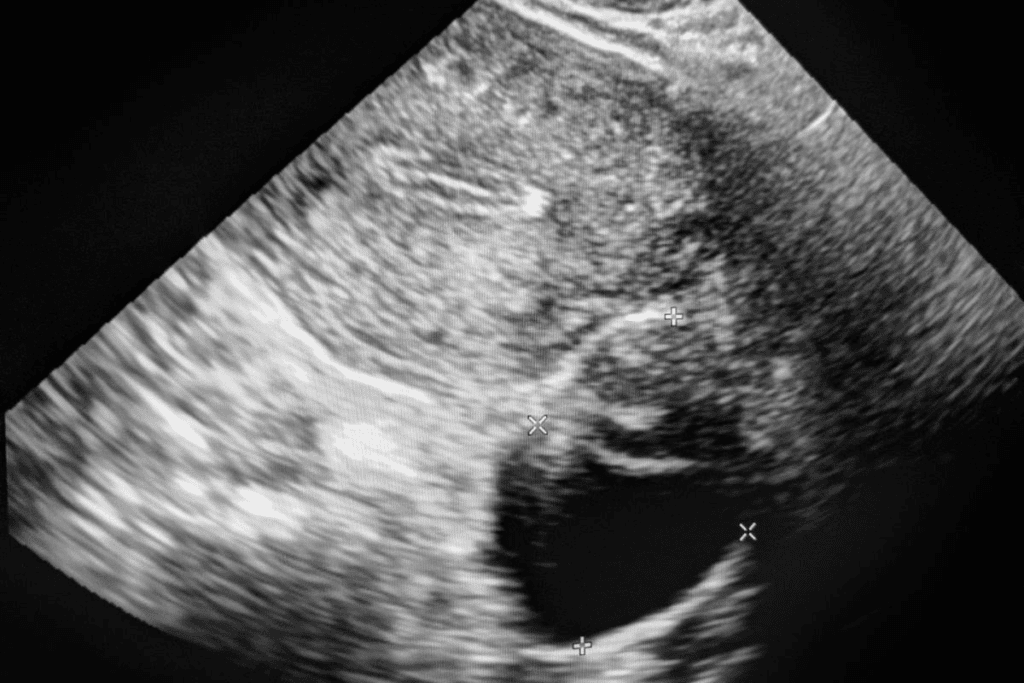

- MRI (Magnetic Resonance Imaging) to see the fibroids and uterus

- Ultrasound to look at the uterus and fibroids

With the catheter in place, we use imaging to guide it to the uterine arteries. We use fluoroscopy, a type of X-ray, for real-time visuals. This helps us place the catheter accurately.